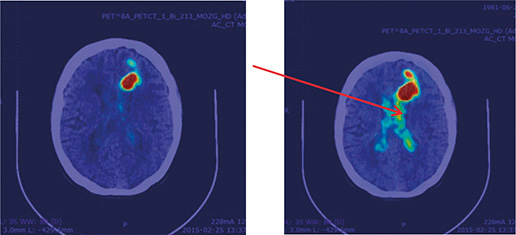

Wprowadzenie Jednym z podstawowych wskazań do leczenia z zastosowaniem radiofarmaceutyków jest rak tarczycy. Jego zastosowanie wiąże się ze zdolnością tyreocytów i komórek nowotworowych tarczycy do aktywnego wychwytu jodków. Innym wskazaniem do leczenia z zastosowaniem radiofarmaceutyków jest leczenie guzów neuroendokrynnych (NEN). Nowotwory z tej grupy charakteryzują się znacznie zwiększoną ekspresją receptorów dla somatostatyny. Najczęściej w terapii…